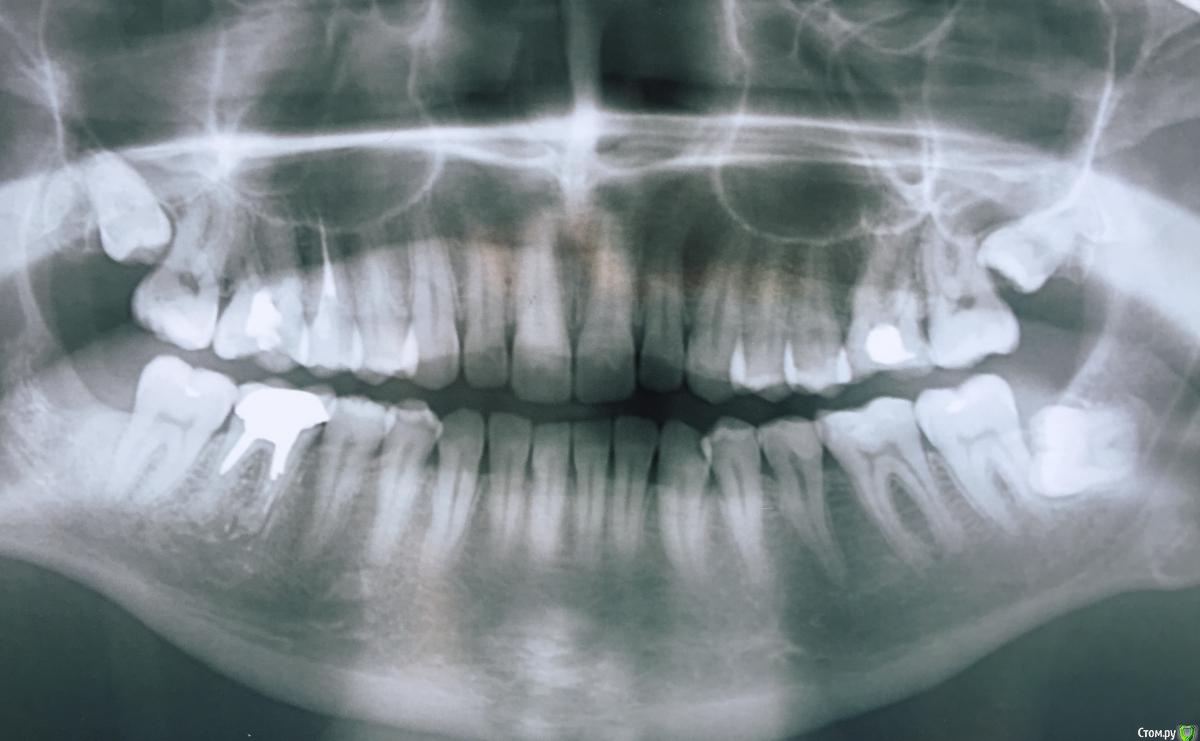

krq Опубликовано 10 декабря, 2018 Автор Поделиться Опубликовано 10 декабря, 2018 (изменено) Снова здравствуйте. Затянул с удалением, в итоге сделал это только недели 3 назад. Вроде лунка заживает и не беспокоит. Тот нарост который на моем рисунке закрашен черным вроде исчез. Но маленький шарик где-то внизу остался. Сегодня сделал снимок. (фото с экрана https://imgur.com/a/Y6uxLau) Что можете сказать по этой части снимка по поводу удаленного 6 зуба?Так же видно что-то на корне 4 зуба(он не беспокоит вообще). Присмотрелся к старому снимку, там тоже есть темная область.Это еще одна киста? :/ Изменено 10 декабря, 2018 пользователем krq Ссылка на комментарий

___49___ Опубликовано 10 декабря, 2018 Поделиться Опубликовано 10 декабря, 2018 Снова здравствуйте. Затянул с удалением, в итоге сделал это только недели 3 назад. Вроде лунка заживает и не беспокоит. Тот нарост который на моем рисунке закрашен черным вроде исчез. Но маленький шарик где-то внизу остался. Сегодня сделал снимок. (фото с экрана https://imgur.com/a/Y6uxLau) Что можете сказать по этой части снимка по поводу удаленного 6 зуба?Так же видно что-то на корне 4 зуба(он не беспокоит вообще). Присмотрелся к старому снимку, там тоже есть темная область.Это еще одна киста? :/ снимок не самого высокого качества, остатков 6го зуба не вижу, в области 4-5 х зубов имеется ментальное отверстие которое на Rснимке для вас может показаться "кистой". 1 Ссылка на комментарий